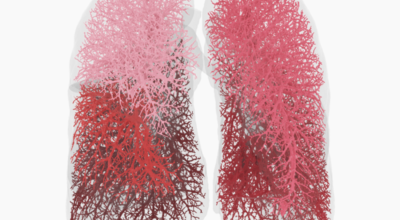

인체가 순조롭게 기능을 발휘하려면 폐 건강이 필수다. 폐는 인체가 효율적으로 움직이는 데 있어 바퀴 안에 있는 톱니 같은 역할을 하기 때문이예요. 산소를 제공하는 폐 기능이 감소하게되면 폐렴이나, 만성 폐쇄성 폐질환(COPD), 천식 등 정도가 심한 호흡기 질환 발생 위험이 증가해요. 이런 질병들은 폐를 공격해 숨쉬기 힘들게 만들어요.

특별히 현대 사회에서 폐는 가장 시달리는 장기 중 한 종류다. 가지가지 공해 성분으로 오염된 공기에 미세 먼지, 황사까지 더하면 폐 안쪽에 있는 허파꽈리(폐포)부터 정도가 심한 훼손을 입습니다. 따라서 폐 건강을 증진시키기 위하여는 폐에 좋은 음식을 섭취할 필요가 있어요.